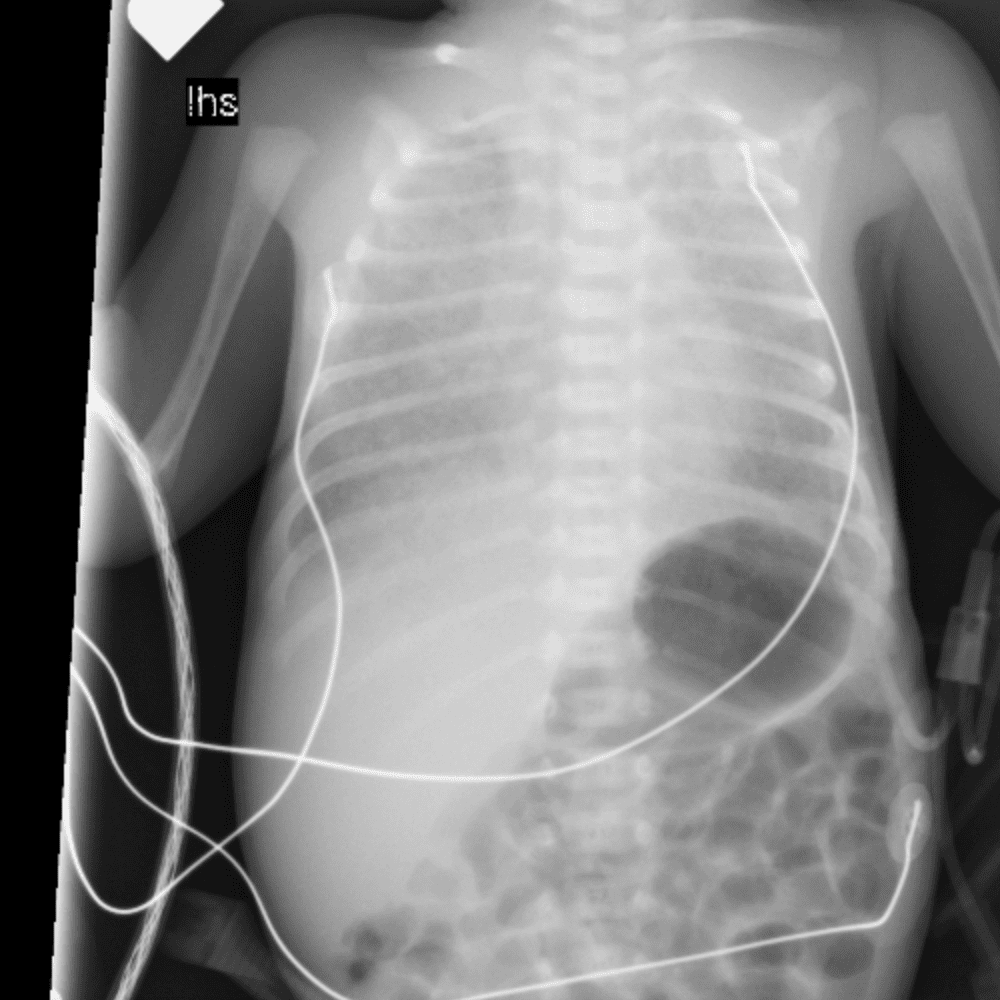

Peds Chest

Practice

Simulates call by including subtle or difficult cases and some normals.

50 cases